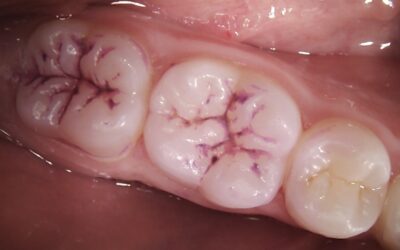

Preventing decay with fissure sealants

As a parent, you want the best for your child's health, and that includes their dental care. One of the most effective ways to help prevent cavities and maintain your child’s oral health is through...